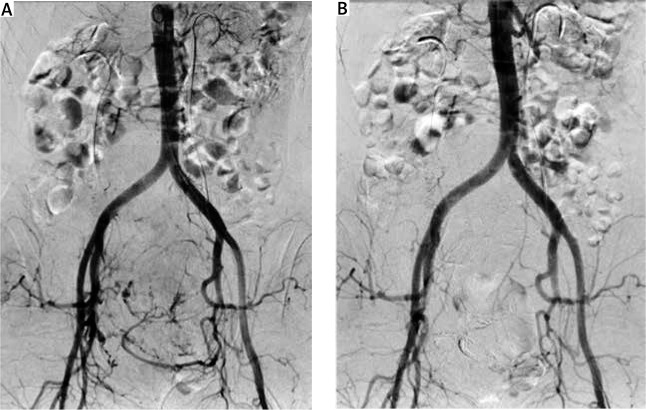

Uterine fibroids are the most common pelvic benign tumours occurring in women of reproductive age. Current treatment options include surgical procedures, pharmacological therapies, and minimally invasive procedures. The most commonly applied and accepted minimally invasive procedure used in the treatment of symptomatic uterine fibroid is uterine artery embolisation (UAE). Uterine artery embolisation is a minimally invasive procedure that can be used either as an auxiliary method or the main treatment method of symptomatic uterine fibroids. We would like to present the application of pre-operative UAE before hysterectomy in anaemic women with giant uterine fibroid (21.9 × 14.9 × 10.4 cm) and HIV-associated nephropathy. Among the possible treatment options for uterine fibroids in cases like the one presented in our manuscript, hysterectomy is the treatment of choice. However, surgical treatment in a patient with severe comorbid conditions and giant uterine fibroid carries serious risk of perioperative complications. Pre-operative UAE decreases such risk by reducing blood loss during hysterectomy and shortening operation/anaesthesia time. Although the benefits of pre-operative UAE before planned myomectomy or hysterectomy in high surgical risk patients with large fibroids has yet to be confirmed in a well-designed clinical trial, this procedure seems to be a promising tool to reduce the risk of perioperative complications in such patients.

Abstract Image